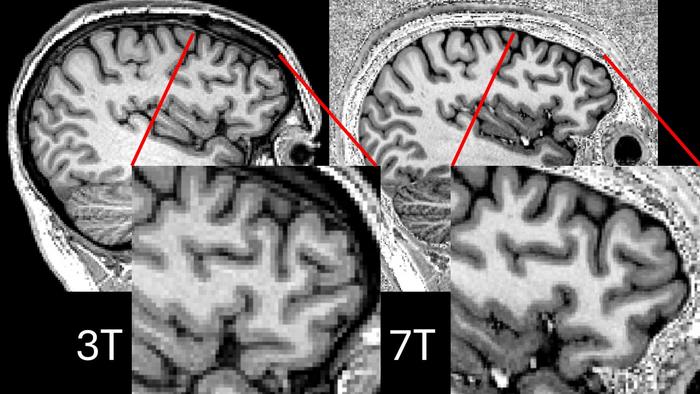

• Cambridge team uses powerful new MRI scans to enable life-changing surgery in first for adults with epilepsy

Cambridge team uses powerful new MRI scans to enable life-changing surgery in first for adults with epilepsy